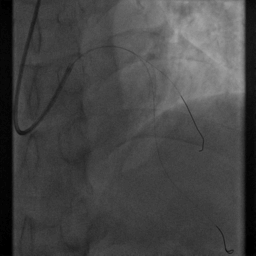

重复造影:前向血流TIMI Ⅲ级,支架近段贴壁欠佳,无夹层、残余狭窄等,D1开口狭窄较先有所加重

7.择2.5*15mm球囊送至D1开口处,以6atm*8s扩张

8.将支架囊送至支架近段,对吻扩张

重复造影:前向血流TIMI Ⅲ级,支架贴壁良好,无夹层、残余狭窄等。